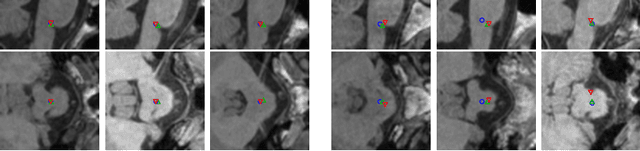

Abstract:We present an automated method for localizing an anatomical landmark in three-dimensional medical images. The method combines two recurrent neural networks in a coarse-to-fine approach: The first network determines a candidate neighborhood by analyzing the complete given image volume. The second network localizes the actual landmark precisely and accurately in the candidate neighborhood. Both networks take advantage of multi-dimensional gated recurrent units in their main layers, which allow for high model complexity with a comparatively small set of parameters. We localize the medullopontine sulcus in 3D magnetic resonance images of the head and neck. We show that the proposed approach outperforms similar localization techniques both in terms of mean distance in millimeters and voxels w.r.t. manual labelings of the data. With a mean localization error of 1.7 mm, the proposed approach performs on par with neurological experts, as we demonstrate in an interrater comparison.